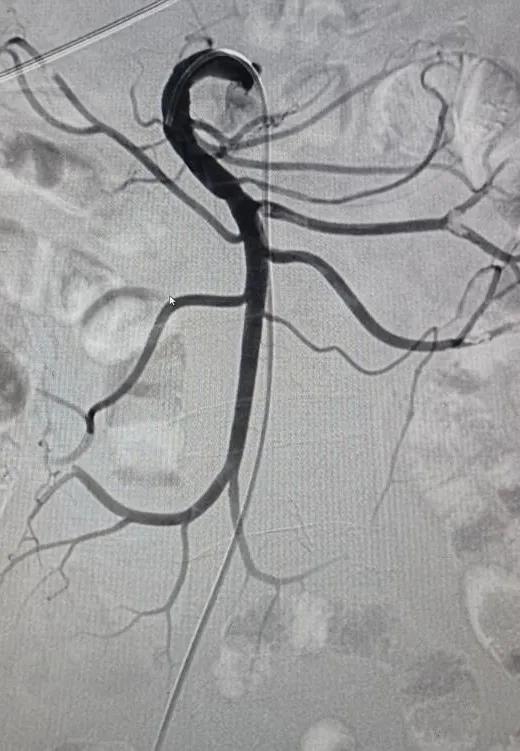

▲肠系膜上动脉栓塞吸栓术前后对比